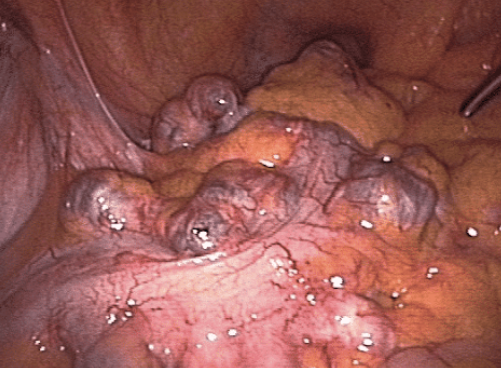

- 게실(Diverticulum): 대장 내벽이 약해지면서 바깥쪽으로 볼록하게 튀어나온 주머니 같은 구조

- 게실염(Diverticulitis): 이 게실에 세균이 침투하거나 노폐물이 고여 염증이 생긴 상태

- **S자 결장(Sigmoid colon)**에 가장 많이 생기며, 좌하복부 통증을 유발함